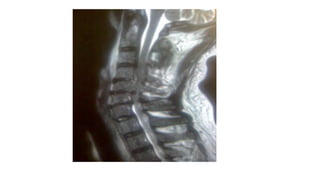

Magnetic resonance imaging

•Magnetic resonance imaging (MRI) is the

best modality for assessing soft tissue

and spinal cord elements.

•It is of greatest use for assessing rotator

cuff tears, spinal stenosis, ligamentous or

meniscal abnormalities of the knee and

wrist joints, osteonecrosis (ie, avascular

necrosis of bone), stress fractures,

osteomyelitis, and subchondral bone

injury in osteoarthritis or meniscal tears.